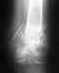

Здравствуйте!10.12.2010 катаясь на горных лыжах уппал, повредил колено. Обратился в травму, порекомендовали тугую повязку, костыли и нимесил. 14.12.2010 на приеме у травматолога, была сделана пункция (70 мл. крови) и наложен лангет, а так же направлен на МРТ. (результаты ниже).

Заключение МРТ:"Разрыв заднего рога внутреннего мениска. Разрыв передней крестообразной связки. Интрамуральное повреждение заднего рога наружного мениска. Импрессионный микроперелом латерального мыщелка бедренной кости. Ушибы мыщелков бедренной и большеберцовой кости, головки малоберцовой кости. Синовиит."Подскажите пожалуйста, обязательно-ли оперативное вмешательство, как срочно необходимо оперироваться и какие могут быть последствия.Заранее спасибо.